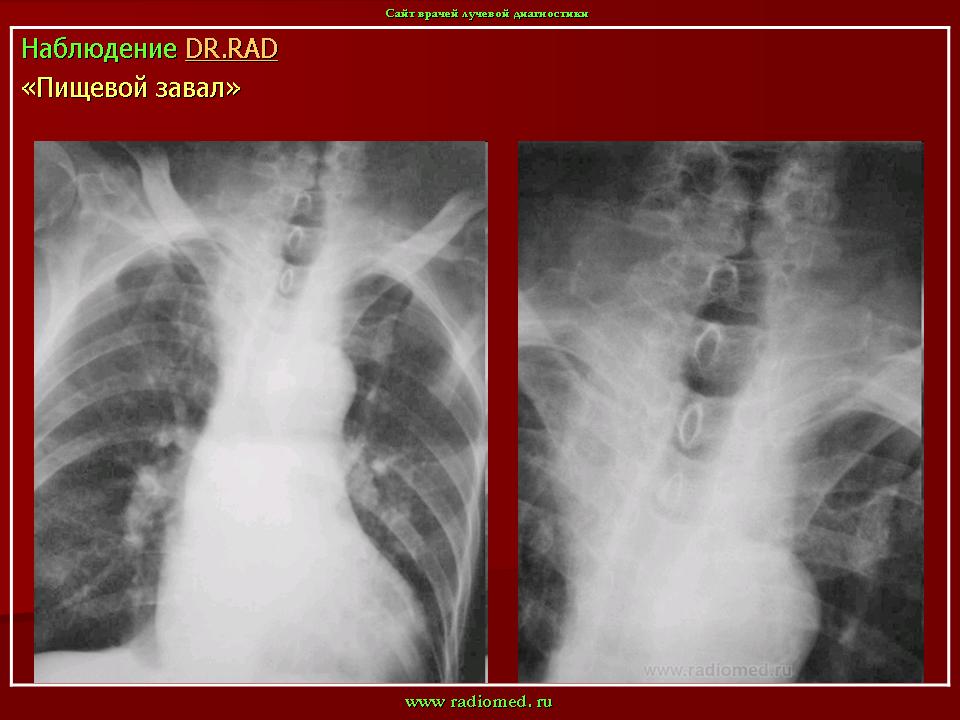

Интересно, а, что такое "пищевой завал"?

И.Бондаренко wrote:

"Пищевой завал" чаще наблюдается у лиц преклонного возраста, по статистике чаще у мужчин. В результате снижения тонуса пищеварительной трубки крупный пищевой кусок, чаще - мясо, просто застревает и обтурирует просвет пищеварительной трубки, чаще на уровне глотки, верхней части пищевода, но на много чаще на уровне 1 физиологического сужения - "рот Килиана".